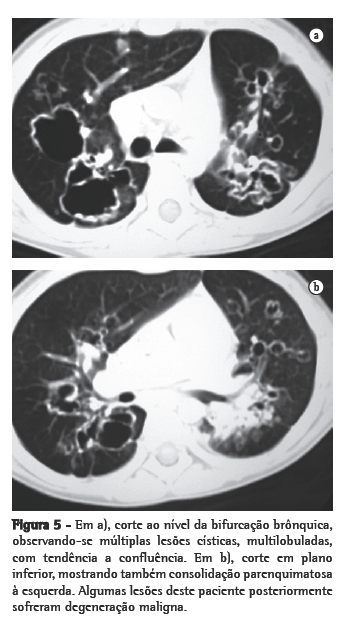

Nos 8 casos foram observadas na TC formações polipóides na traquéia. Em 1 deles, identificou-se também uma lesão em brônquio principal. Sete pacientes mostravam comprometimento do parênquima pulmonar. Em todos foram observadas lesões nodulares escavadas, com contornos internos irregulares, e paredes de espessuras variadas, com aspecto multilobulado em 6 casos, e com confluência das lesões em 5 deles (Figuras 1 a 5). Nódulos sólidos foram vistos em 6 pacientes, Em apenas 1 dos casos foram vistos níveis líquidos. As lesões predominaram nas bases em 3 pacientes, nos terços médios em 2, e em 2 não havia predomínio de distribuição. Em 1 dos pacientes, foi observada associação com massa, e em outro, com consolidação. Neste último paciente (Figura 5) foi constatada degeneração maligna em múltiplas lesões. Sinais de aprisionamento aéreo também foram observados em 1 caso. Em nenhum deles detectou-se linfonodomegalia ou derrame pleural.

A TC, particularmente com aquisição volumétrica (espiral), é superior às radiografias de tórax no reconhecimento de nódulos ainda pequenos, nas fases iniciais de disseminação pulmonar, por sua melhor caracterização e visualização de vegetações nodulares traqueobrônquicas. Os achados tomográficos incluem estreitamento nodular, focal ou difuso, da via aérea. Os nódulos crescem na superfície mucosa, e sua extensão intraluminar é melhor avaliada por TC.(3) São alterações facilmente correlacionadas à doença quando se dispõe da história clínica de papilomatose.(4) Outros achados relacionados à obstrução das vias aéreas e/ou infecções associadas são atelectasias, consolidações, aprisionamento aéreo e bronquiectasias.(2-4) Na nossa casuística, formações polipóides na traquéia foram observadas em todos os exames tomográficos. Sete pacientes mostravam comprometimento do parênquima pulmonar, caracterizado por lesões nodulares escavadas, com contornos internos irregulares, e paredes de espessuras variadas, com aspecto multilobulado e tendendo à confluência. Nódulos sólidos foram vistos em 6 pacientes. Em nenhum deles detectou-se linfonodomegalia ou derrame pleural.